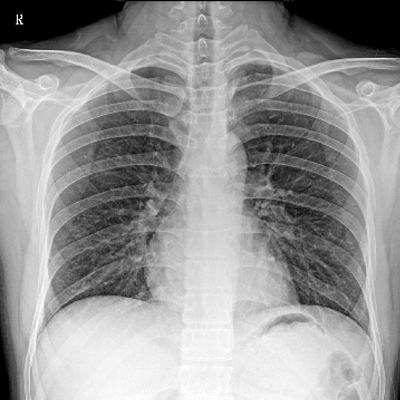

輕量化設(shè)計(jì) 小巧靈活 PLX5100

用于影像科、急診室、病房、ICU、手術(shù)室等多場(chǎng)景應(yīng)用。

● 數(shù)字化無(wú)線平板成像,操作簡(jiǎn)便,成像質(zhì)量高

● 配備移動(dòng)筆記本,無(wú)線圖像采集,無(wú)線PACS傳輸